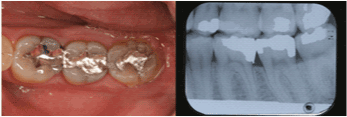

| Mandibular Left Second

Molar |

2 |

54.8% |

|